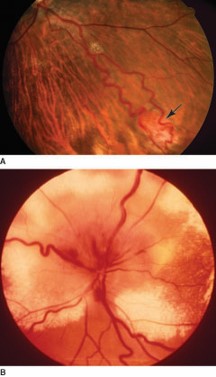

Retinal angiomatosis (von Hippel disease). (A) Well-developed retinal lesions in this disorder appear as a discrete retinal angioma (arrow) with an enlarged feeder artery and draining vein, as seen in this photograph. (B) Retinal angiomas can cause an exudative retinopathy with severe visual consequences, as seen in a different patient with retinal angiomatosis. Note the retinal detachment above the optic disc and extensive subretinal and intraretinal exudates.

Source: Martin TJ, Corbett JJ. Practical Neuroophthalmology; 2013.